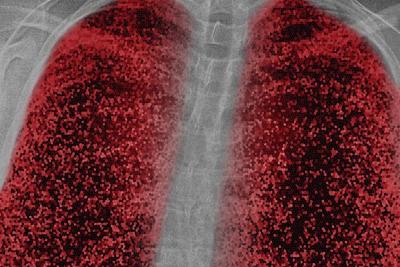

निमोनिया - दरवर्षी हजारो लोकांना निमोनिया होतो. हे एक घातक इन्फेक्शन आहे. ज्यामुळे श्वास घेण्यादरम्यान छातीतमध्ये वेदना होतात. अमेरिकन लंग्स असोसिएशननुसार, खोकला किंवा श्वास घेताना वेदना जास्त होतात.

लंग्समध्ये इन्फ्लामेशन असणं - वेगवेगळे बॅक्टेरिया आणि व्हायरस फुप्फुसांमध्ये इन्फेक्शन निर्माण करू शकतात. हळूहळू यामुळे लंग्स मेंब्रेनमध्ये इन्फ्लामेश येते आणि श्वास घेताना किंवा खोकला आला तर वेदना जाणवतात.